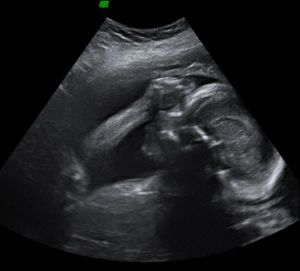

Holnap írok, addig néhány kép:

Kép 2D-n

Kép A bizonyíték - tényleg fiú